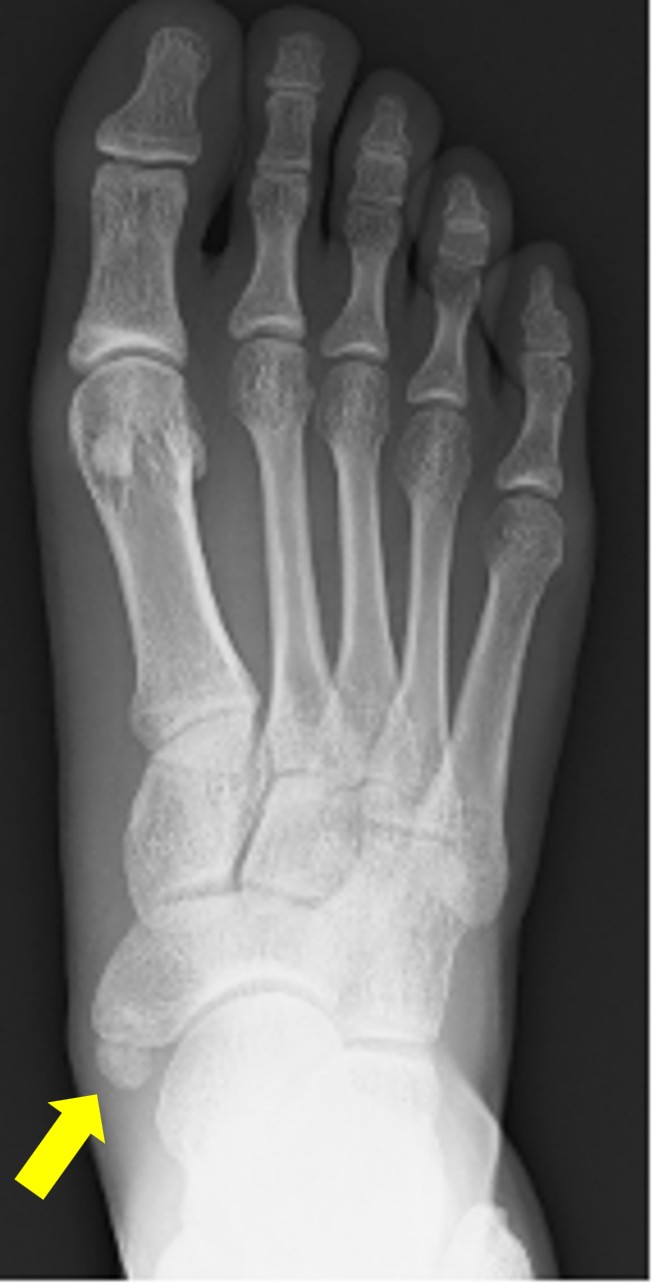

有痛性外脛骨

術前レントゲン写真(矢印が外脛骨)